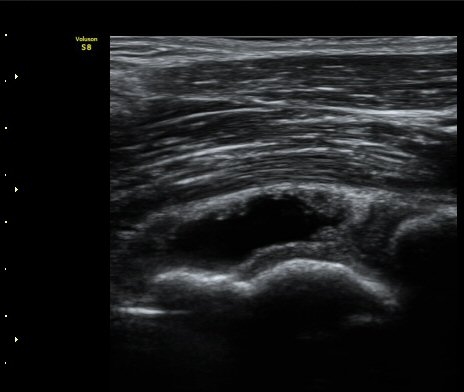

ÃÊÀ½ÆÄ °Ë»ç